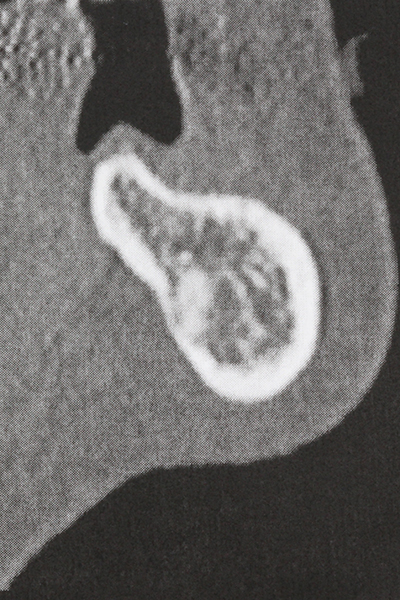

Fig. 17a: immagine TC di un'osteotomia con promozione di crescita immediatamente adiacente a...

Fig. 17b: dotto dell'alveolo dentale con irritazione del nervo (vista laterale e coronale).